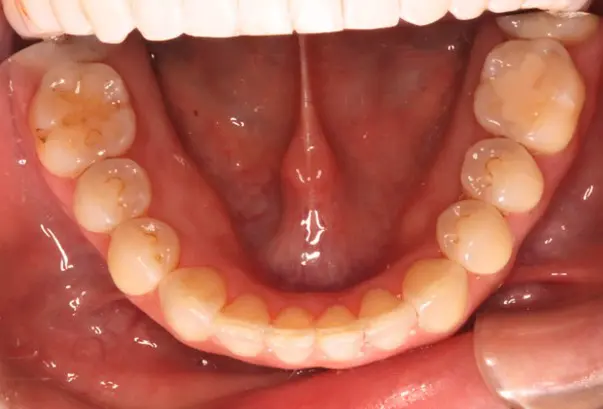

Before

After